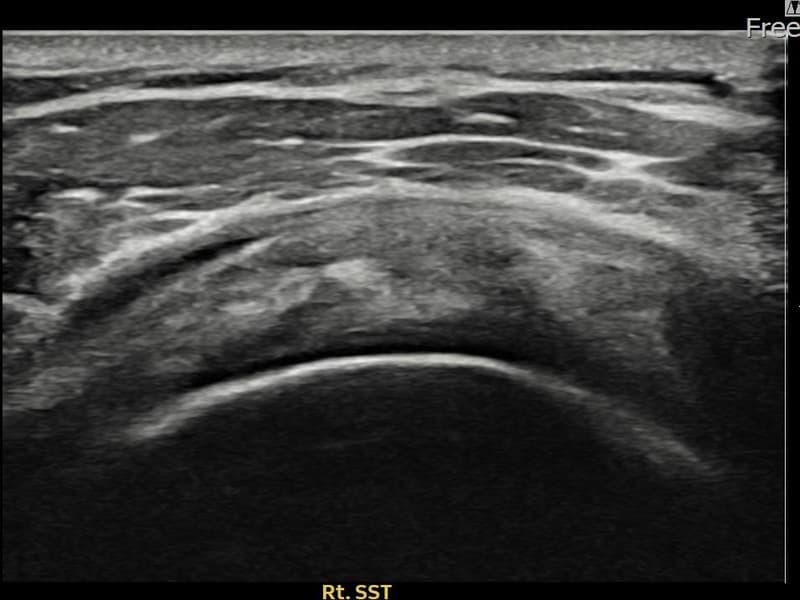

시술 전 초음파 측정 결과 파열 크기는 7mm × 3mm (힘줄 두께의 약 28% 결손)로 확인되었습니다. 시술 전 초음파에서 우측 견갑하근건 관절면측의 에코 단절과 힘줄 결손 소견이 확인되었습니다. 시술 후 초음파에서 파열 부위에 재생 조직이 형성되고 힘줄 연속성이 회복된 것이 관찰되었습니다.

30대 후반 남성 환자분으로, 우측 어깨 앞쪽 통증과 함께 팔을 안쪽으로 돌리거나 등 뒤로 보내는 동작이 어려워 내원하셨습니다. 헬스 훈련 중 부상 이후 증상이 시작되었으며, 견갑하근건 손상은 극상근건 손상에 비해 발견이 늦은 경우가 많아 주의가 필요한 부위입니다. 초음파 검사에서 우측 견갑하근건 관절면측 부분파열이 확인되었으며, 초음파 유도 하 축소봉합술을 시행하였습니다. 시술 후 내회전 강화 재활 운동을 통해 꾸준히 회복하였고, 시술 후 추적 초음파에서 힘줄 연속성이 회복되어 정상 생활에 복귀하셨습니다.